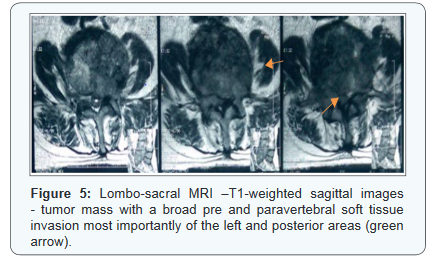

Lombo-sacral MRI showed a 90x52x77mm advanced lesion process, involving L4, L5 and S1 vertebrae, causing a cuneiform compression of L5, with a broad pre and paravertebral soft tissue invasion most importantly of the posterior arches of L4, L5 and S1 vertebrae, extension into spinal canal with an invasion of the roots of caudaequina nerves and infiltration of sacred holes with a corporal metastasis of L3 (Figures 3-5). A US-guided percutaneous Tru-cut biopsy of the tumor was performed. The histopathological examination revealed thyroid follicles filled with colloid material. The follicle cells were generally cuboid and round-oval shaped with hyperchromatic nuclei showing mild pleomorphism which was consistent with metastatic FTC.